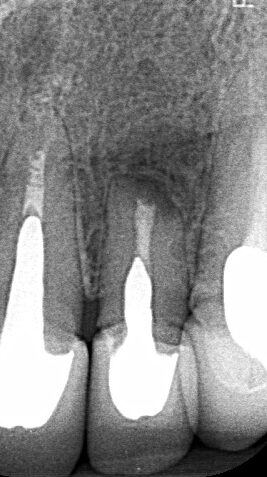

She was worried about the consequences of losing her tooth and decided to seek advice from me to determine whether it was possible to treat this tooth again. We agreed to perform surgery to remove the infection and also encouraged healing by adding her own blood plasma to the bone space to help with healing. Seven months later, we were delighted to see the infection had cleared and bony healing occurring. The tooth was saved and is still going two years later!

This meant she avoided the need to take the tooth out and face more expensive options to restore the gap!